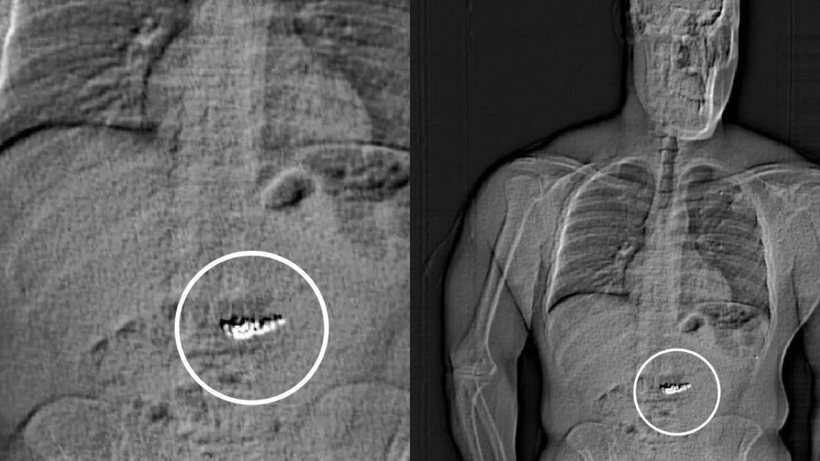

Şüpheli, cezaevine götürüldüğünde yapılan vücut taramasında midesinde "yabancı cisimler" olduğu tespit edildi. Polis, bunların çaldığı elmas küpeler olduğunu düşünüyor, ancak durumu doğrulamak için "doğal sürecin tamamlanmasını" beklemek zorunda.